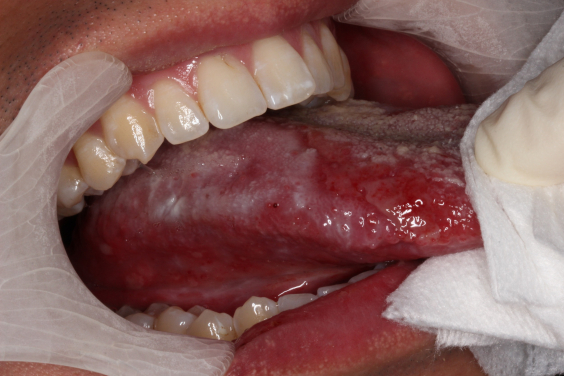

Oral cancer often develops from white patches clinically known as oral leukoplakia (OL) and oral lichenoid mucositis (OLM). These white patches may appear long before a diagnosis of oral cancer, and their early detection and continuous monitoring are crucial to prevent the development of cancer. However, it is sometimes challenging to predict which OL/OLM lesions will develop into oral cancers as the global risk rates of progression from OL/OLM to cancer vary from 0.4 to 40.8%.